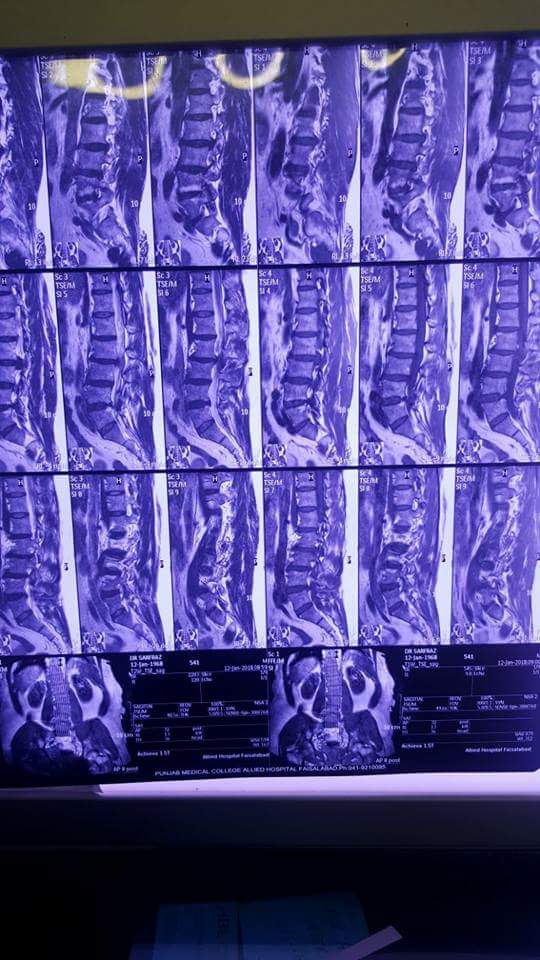

Lower back pain couple of years. Pain right thigh right knee joint. No recent trauma.

Thank you Dr sarfraz for asking. Although the radiographs and MRI are showing degenerative changes of spine and disc bulge as well, but a clinical examination is required. Cauda equina syndrome, characterized by loss of bladder or bowel function and saddle Anesthesia warrants emergency surgery. All other procedures are elective, depending on the clinical significant finding.

mri shows L3/4 disc prolapse.